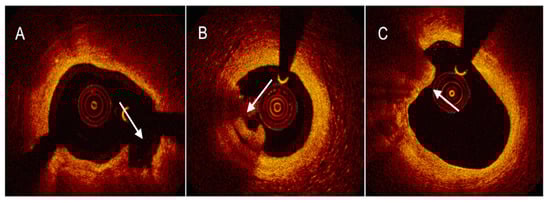

4.2. Optical Coherence Tomography